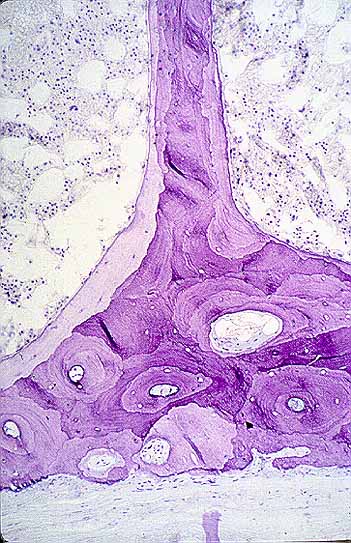

La placa de crecimiento es una estructura con forma de disco que se halla intercalada entre la epífisis y la diáfisis. En la placa de crecimiento se distinguen dos regiones, una central y otra periférica. La región central está constituida por cartílago hialino en el que se distinguen, desde la epífisis a la diáfisis, cuatro zonas: zona germinal, zona proliferativa, zona de cartílago hipertrófico y zona de cartílago calcificado2.

Zona germinal (capa de reserva o de reposo): Es la zona más cercana a la epífisis. Está constituida por células cartilaginosas aisladas de forma oval. En esta capa se observan mitosis y existe una intensa síntesis de matriz extracelular

Zona proliferativa: Se halla constituida por células cartilaginosas en forma de cuña cuyo eje mayor es perpendicular al del hueso. Estas células se disponen en columnas paralelas al eje longitudinal del hueso. En esta zona también se observan mitosis y existe una intensa síntesis de matriz extracelular. Las células de cada columna parecen dividirse al unísono pero de manera asicrónica con respecto a las de las columnas restantes.

Zona de cartílago hipertrófico: Los condrocitos de esta zona maduran, adquieren forma redondeada y su tamaño aumenta a medida que se alejan de la epífisis.

Zona de cartílago calcificado: En esta zona la matriz cartilaginosa se mineraliza. El núcleo de los condrocitos pierde cromatina (cariolisis) y su citoplasma se vacuoliza. Finalmente estas células mueren y desaparecen por lo que en el extremo de cada columna se observa un espacio vacio rodeado por matriz cartilaginosa calcificada que corresponde al que anteriormente ocupaba un condrocito. Sobre esta matriz calcificada los osteoblastos del estroma de la medula diafisaria depositarán hueso plexiforme (osificación de tipo endocondral). En el curso del modelado óseo este hueso inmaduro será sustituido por hueso laminar.

La región periférica de la placa de crecimiento se denomina zona de Ranvier. Esta zona es un anillo de sección triangular y base externa que rodea la región central de la fisis. La zona de Ranvier se halla constituida por células inmaduras con diferenciación condroblástica y osteoblástica. Las primeras podrían contribuir al crecimiento circunferencial de la placa de crecimiento y las segundas podrían contribuir al crecimiento en longitud de la cortical diafisaria.